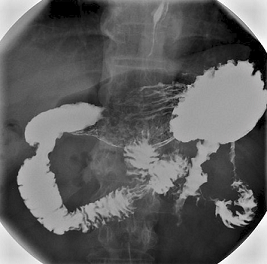

Barium meal stomach X-ray

© By Lucien Monfils (Own work) via Wikimedia Commons